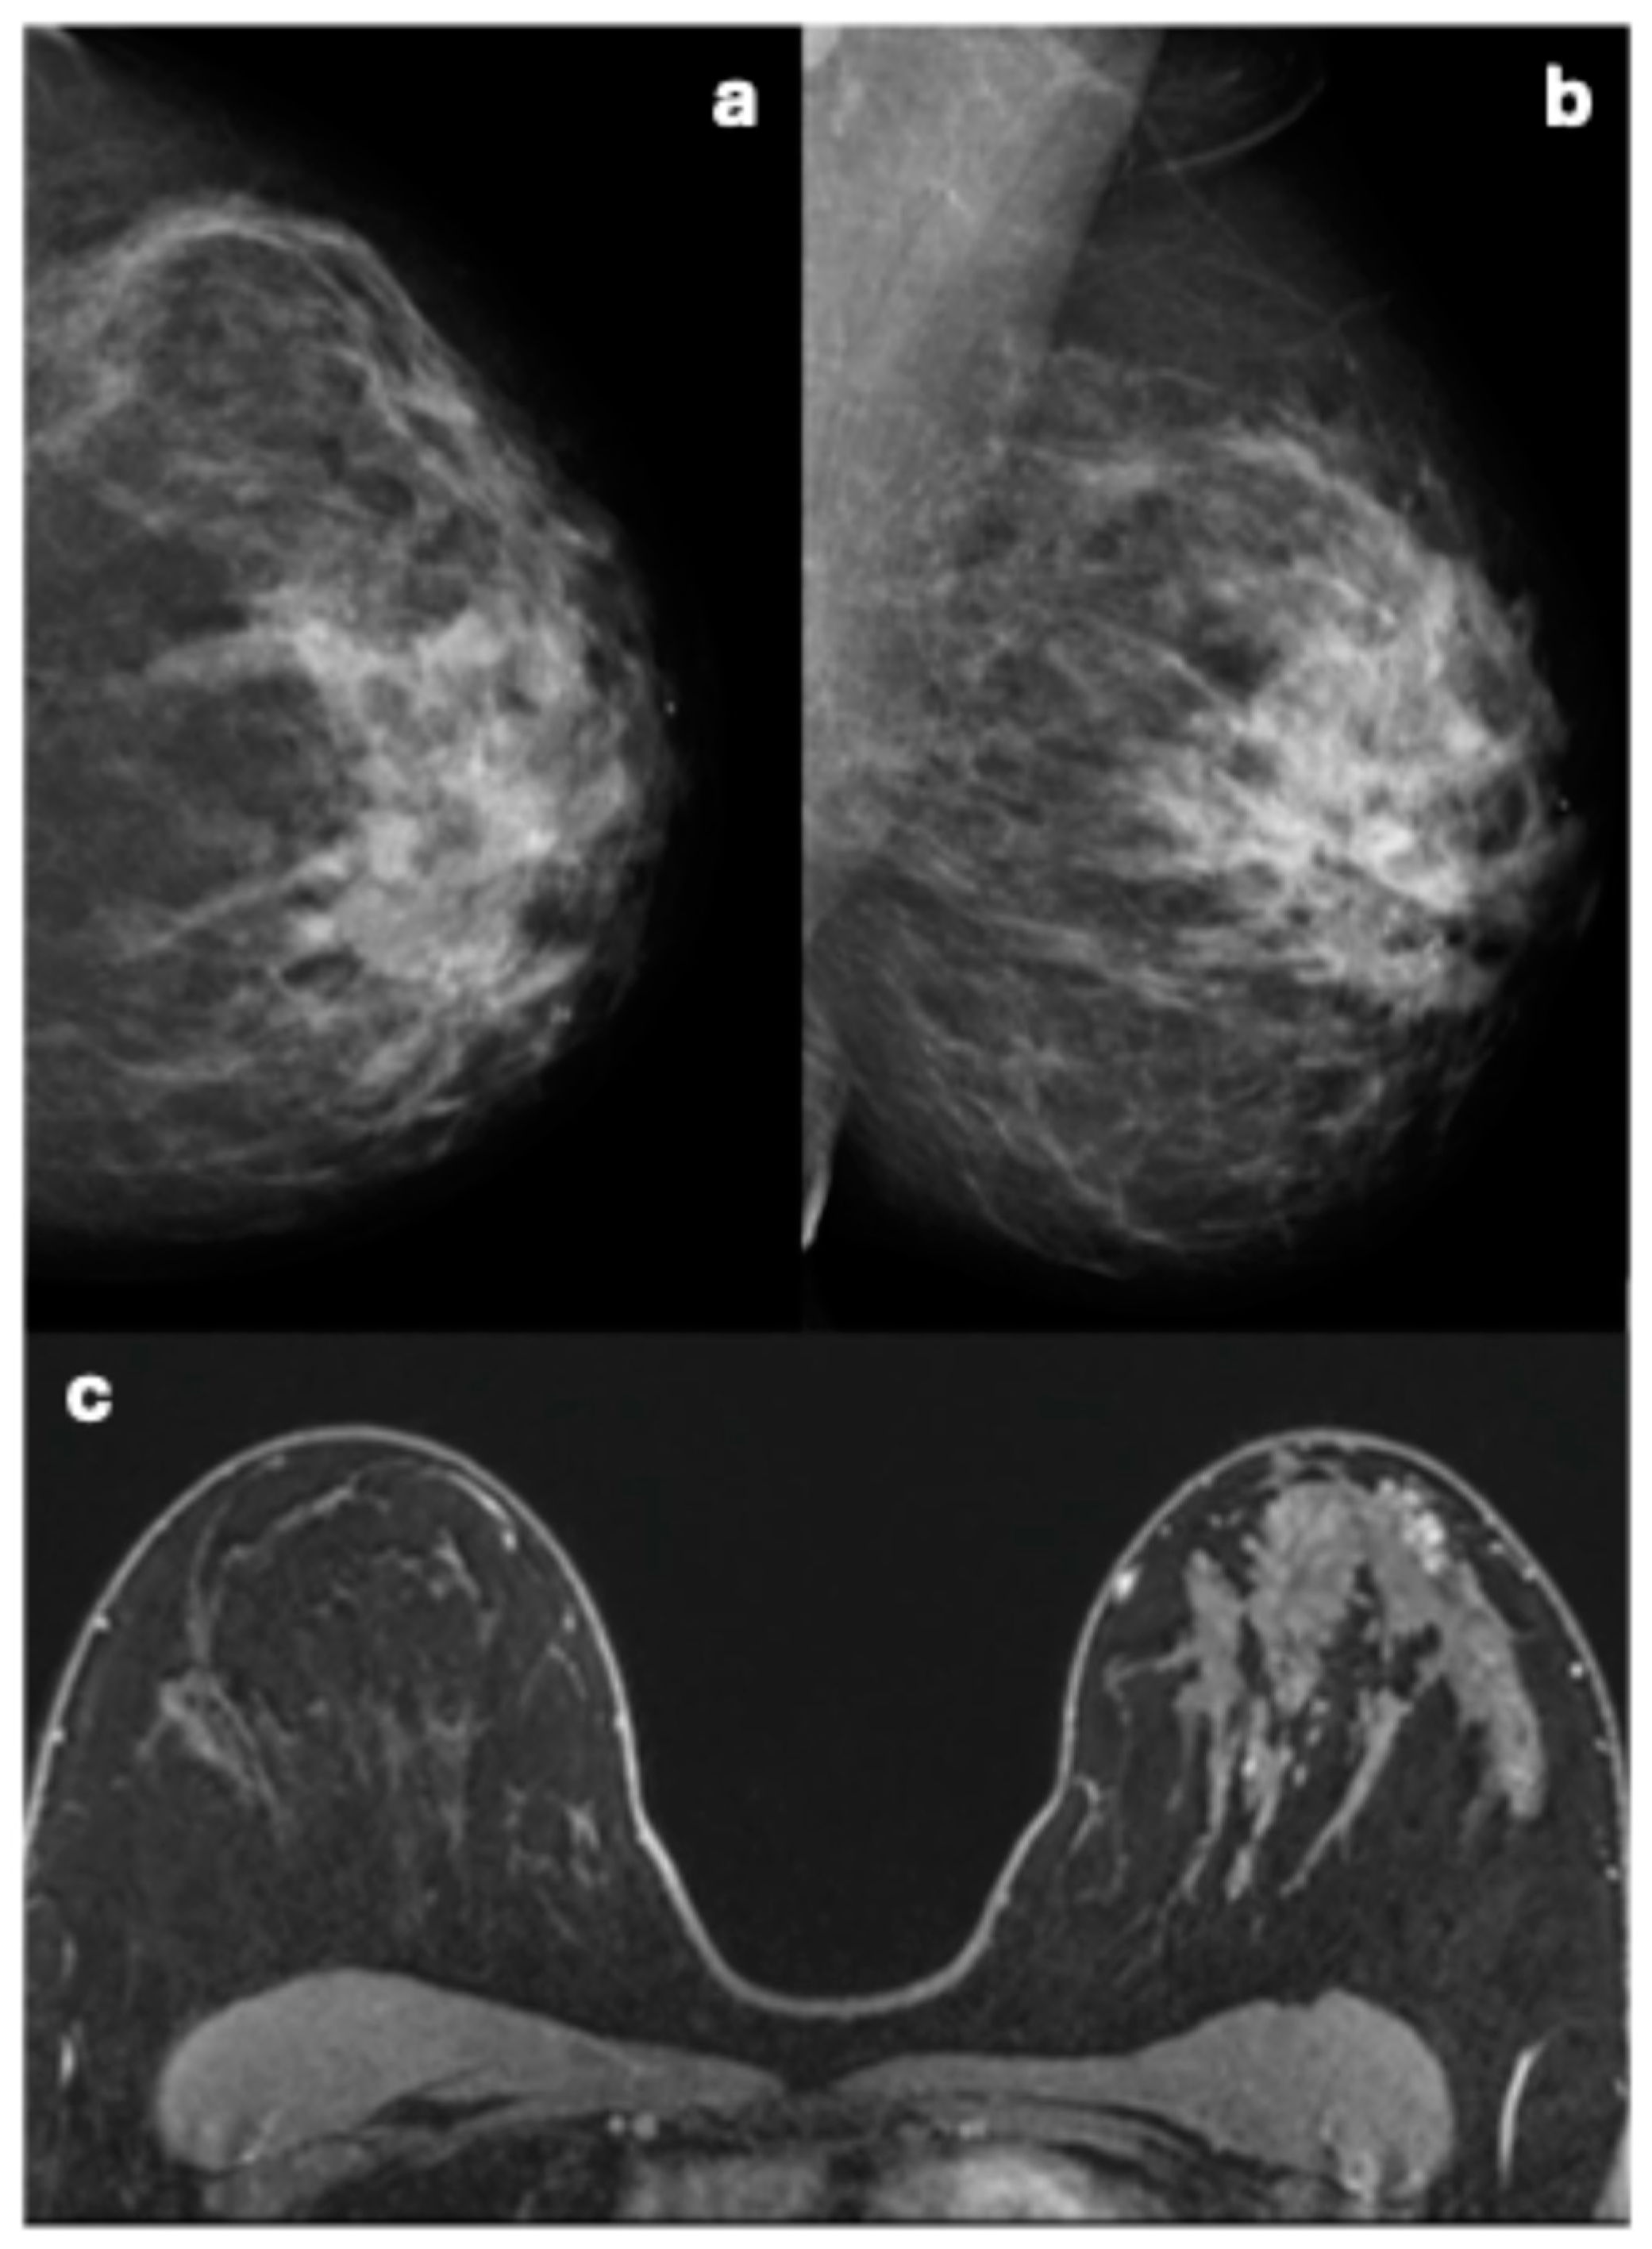

These five breast cancers undetected by mammography occurred in three women with breast density classified as C (n = 1) or D (n = 2). These breast cancers were described at MRI as irregular masses (N = 3) with irregular margins and heterogeneous enhancement patterns (three invasive carcinomas NST), one focal non-mass enhancement (NME) with heterogeneous internal enhancement (invasive carcinoma NST), and one segmental NME with clumped internal enhancement (DCIS) (Figure 6).

Figure 6.

Imaging of a woman with dense breasts illustrating the limitations of mammography and the sensitivity of MRI. (a) Cranio-caudal and (b) medio-lateral oblique mammography views show no identifiable or suspicious lesion. However, MRI (c) reveals a segmental, clumped non-mass enhancement (NME) lesion in the left breast, characterized by a type III kinetic curve. Pathology subsequently confirmed this lesion to be ductal carcinoma in situ (DCIS).